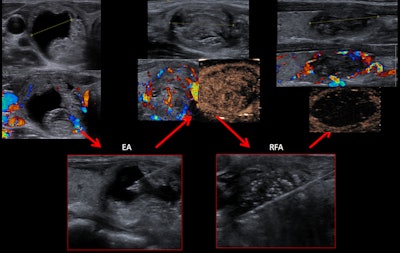

In theory, moving shots create a cylindrical effect in the RF ablation, but, in real cases, backward movement is based on step-by-step intervals that create a beaded cone-shaped cylinder, they explained. CEUS is performed before removing the needle from the nodule, and this defines triangular zones at the periphery without ablation and allows completion of the treatment. It is essential to prevent the needle or the electrode from moving when the patient swallows or talks.

"Elastography performed in several of our patients after RF ablation shows that there was an important component of fibrosis during the follow-up," the authors pointed out.

Also, they observed that the usefulness of ethanol ablation in solid-cystic nodules has reemerged with the introduction of RF ablation.